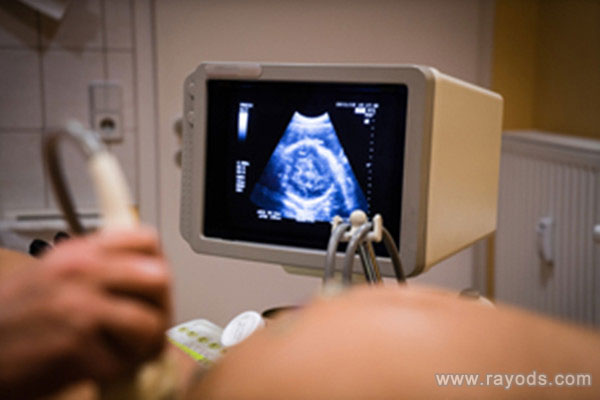

孕检nt胎儿不配合怎么办 怀孕之后,大大小小的检查数不胜数,准妈妈都快忙不过来了。说起产检,准妈妈记忆犹新的应该是排畸检查,这也是准妈妈最关注的检查项目。怀孕早期的nt检查;怀孕中期的四维彩超检查;怀孕晚期的唐氏筛查等,这些个重点产检一个也不能少。

怀孕11周-13周6天前,孕妈妈必做的nt检查,是怀孕早期重要的排畸检查,一定不能错过了。若是做nt检查时,胎儿宝宝不配合怎么办呢?

做nt检查,无需空腹做。NT检查,是通过B超看胎儿颈后透明带厚度一项检查,进食和饮水都不会影响其检查结果。

做nt检查,无需憋尿做。NT检查是腹部彩超检查,孕11-14周之间做,此时羊水已经形成了,所以准妈妈在检查时无需憋尿。